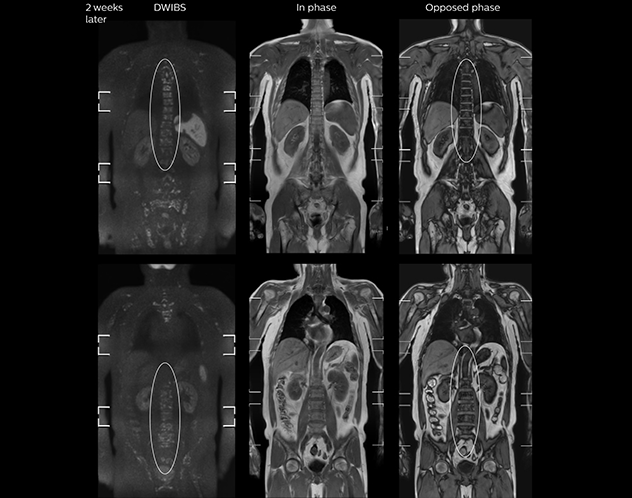

“When we limited the scan coverage to the area from neck to femur, we could fit more clinical information in approximately the same scan time. So, we added coronal mDIXON, sagittal T1-weighted, and sagittal STIR sequences to our examination, instead of performing only axial DWIBS and coronal single-shot TSE scans.”

The single shot T2-weighted TSE images are used for morphology and compared to DWIBS images to identify T2 shine-through. Sagittal STIR images are used in patients with inflammation or bone metastasis.

“Switching to coronal DWIBS – rather than axial – further shortens scan time,” says Mr. Naka. “Important is that a dS SENSE factor of 5 shortens exam time while high image quality can be maintained, thanks to Ingenia’s dStream architecture.” He adds that the coronal orientation also avoids artifacts that are specific to combining axial images.

“When we use a coronal DWIBS acquisition, we can perform a full whole body examination, including other required sequences, within 30 minutes,” he says.

“This is considerably faster than the previously used exam with axial whole body DWI, which took more than 45 minutes,” he notes. “A shorter exam is more patient-friendly and allows us to also use it on patients in poor health who would have difficulty tolerating a long exam. Limiting the exam time is also helpful for scheduling, because it fits in a normal single exam timeslot.”